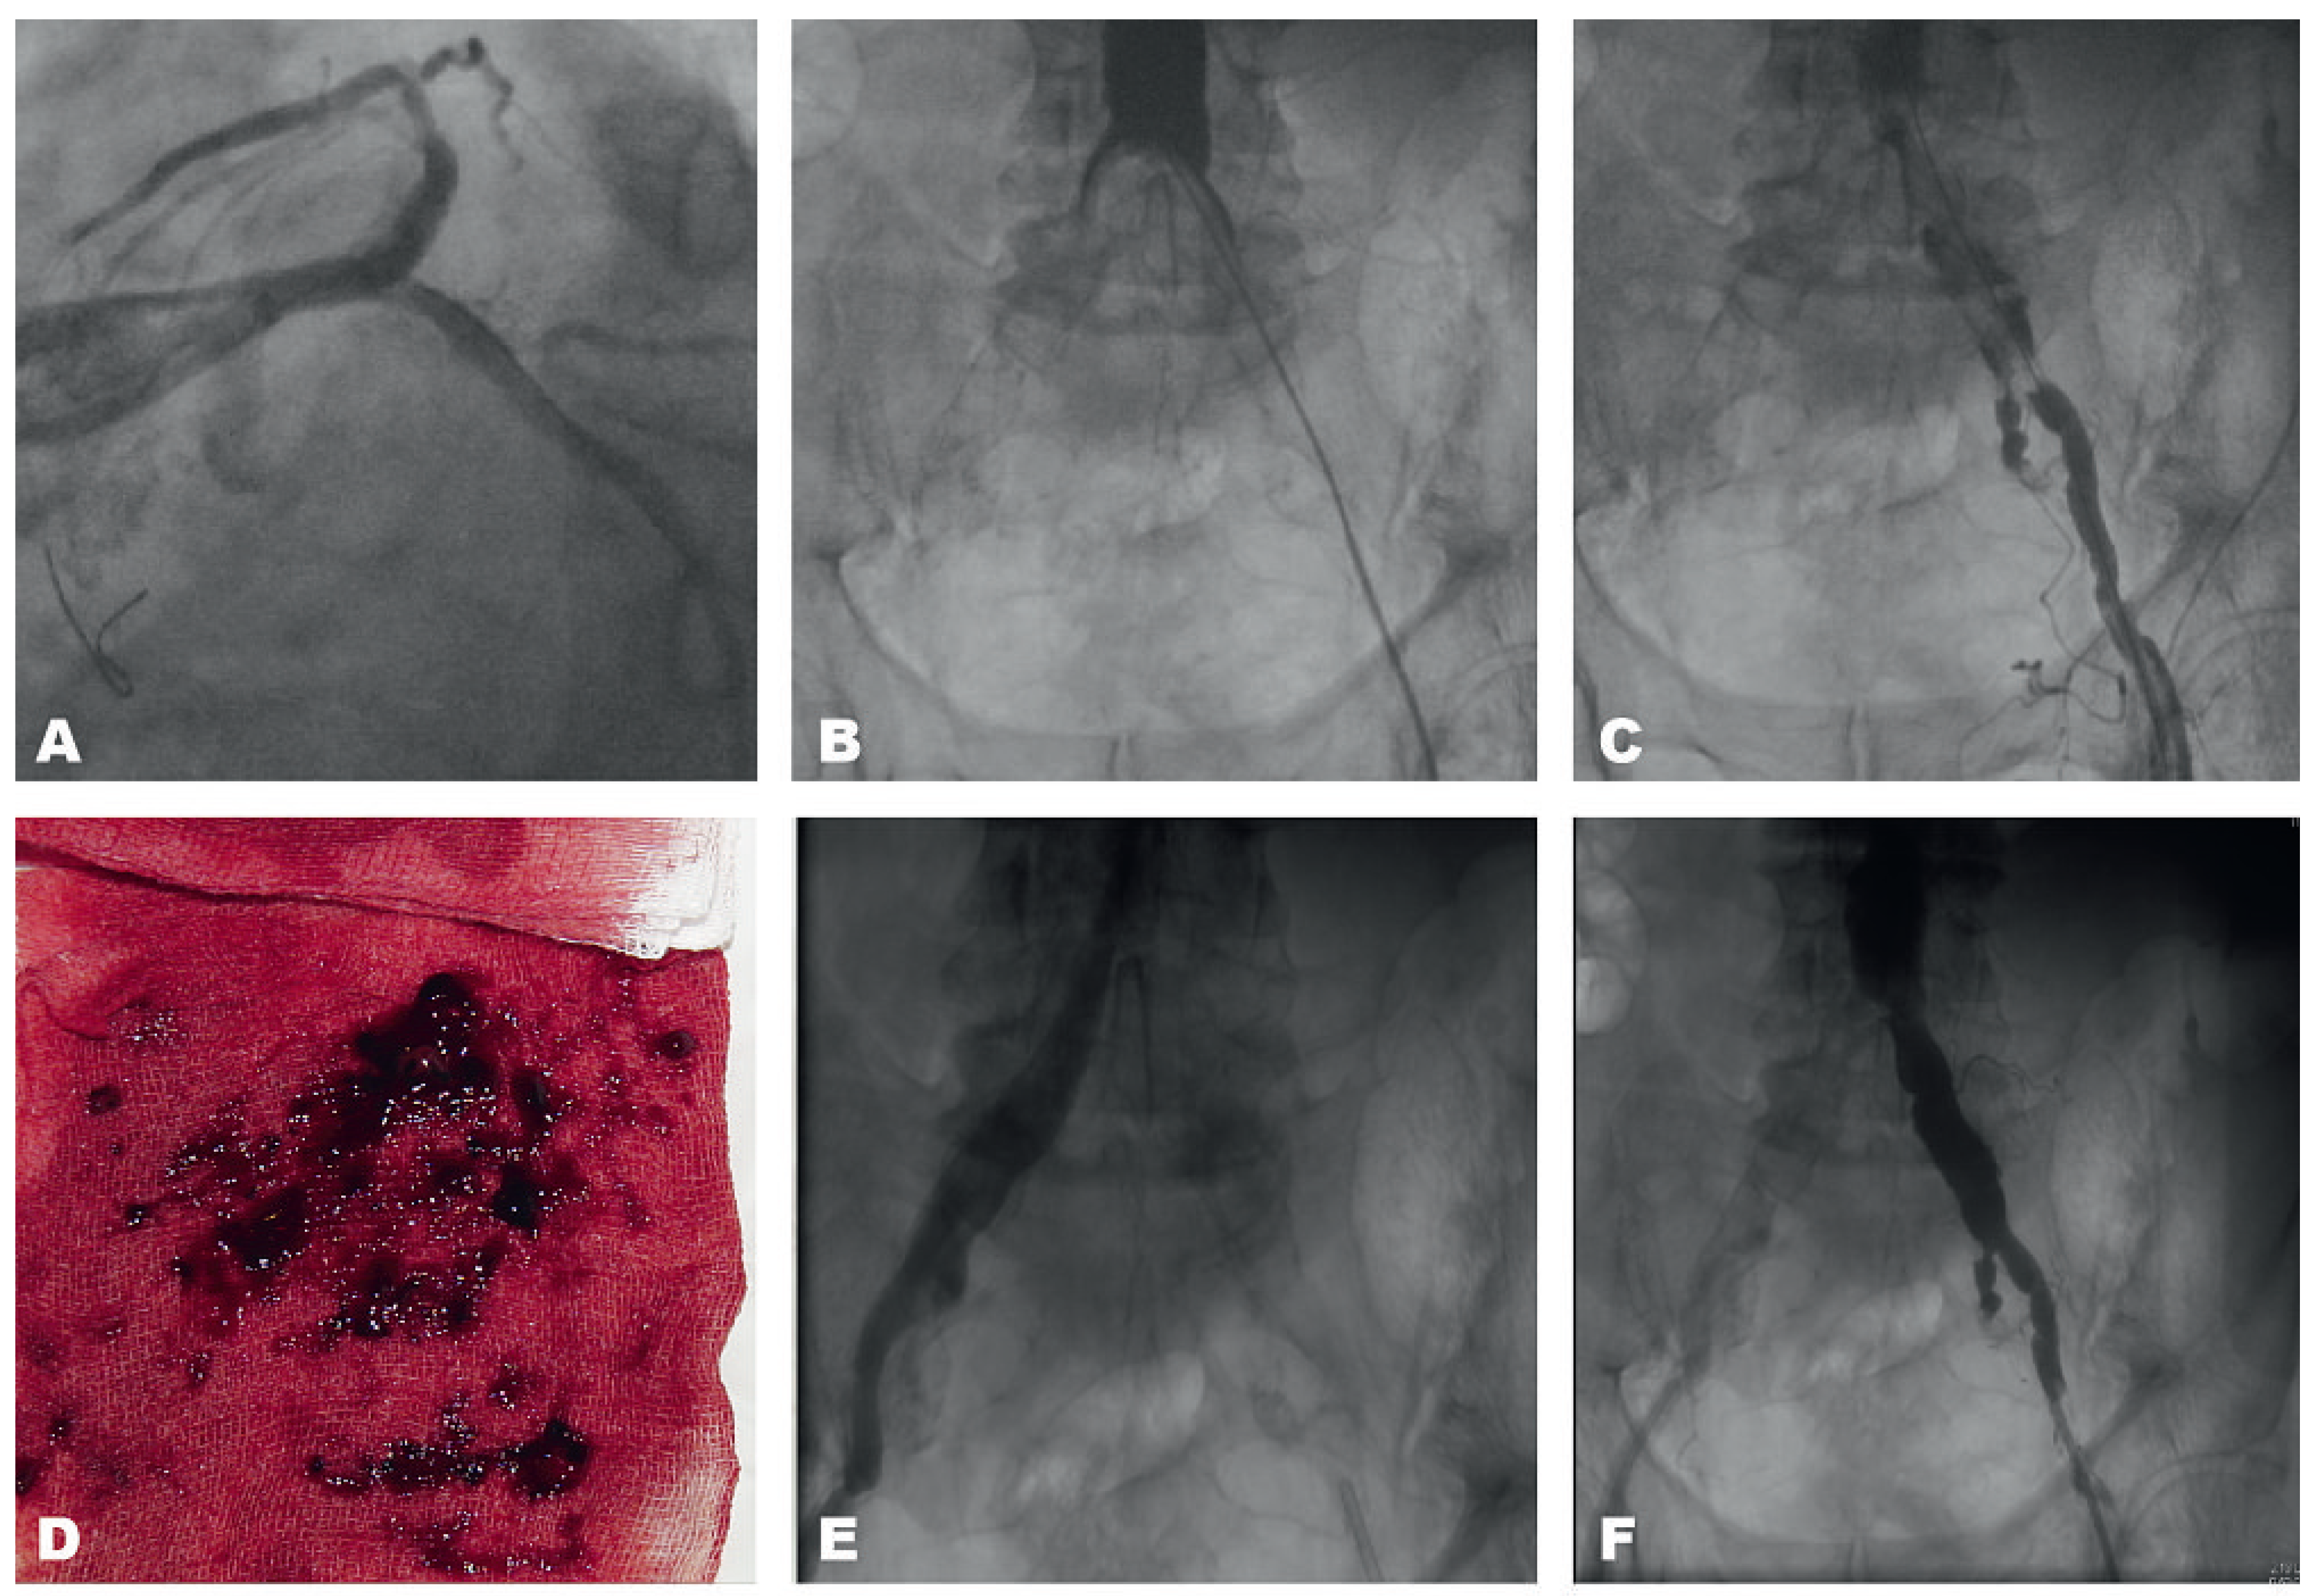

Acute Leriche Syndrome in an 83-Year-Old Man with Non NSTEMI After Cardiac Resuscitation Because of Ventricular Fibrillation